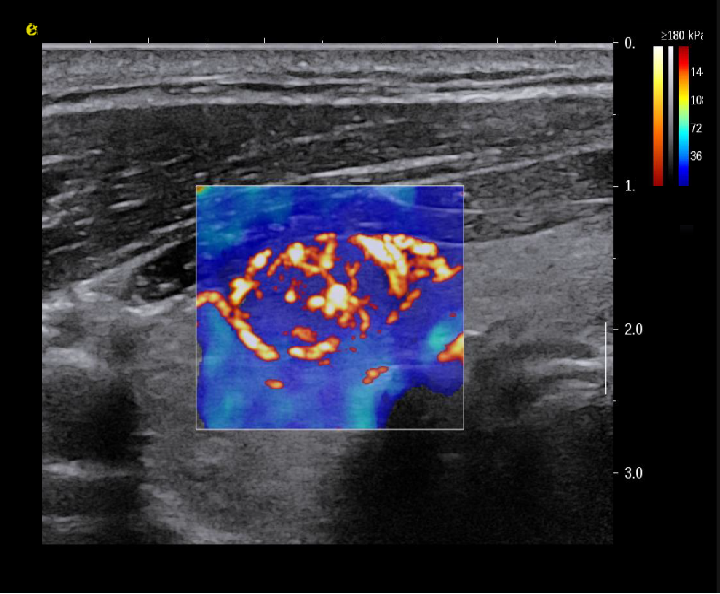

平面波超微细血流显像

能够提供更多真实的组织细小及末梢血管的血流信息,直观的观察组织内部的血管架构及血流形态的情况,提供临床更多有价值的诊断信息。

临床应用:

肿瘤鉴别诊断(肝脏、肾脏、甲状腺、乳腺、  涎腺等)

淋巴结评价(炎症、肿瘤)

image.png